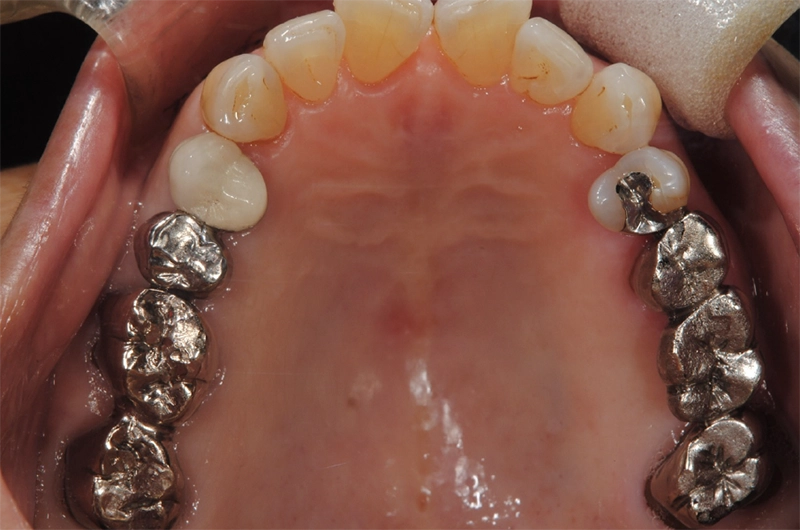

| 主訴 | 歯が抜けている。 入れ歯のところをインプラントしたい |

|---|---|

| 診断名 | 歯の欠損、義歯不適合 |

| 年齢・性別 | 63歳・男性 |

| 治療期間・回数 | 1年3ヶ月・33回 |

| 治療方法 | 精密根管治療、ジルコニアクラウン、GBR、インプラント、ホワイトニング |

| 費用 | 3,949,000円 最高プラン (費用を抑えたプランも提案可能) |

| 治療上のリスク |

|